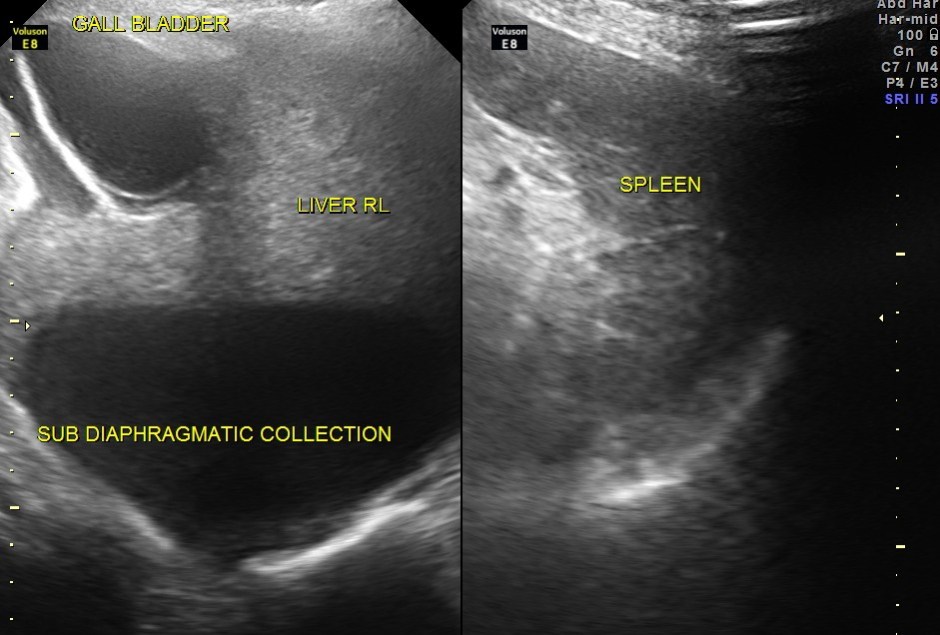

grossly distended gallbladder , with sludge and gallstones and fluid around the gall bladder.

SUB DIAPHRAGMATIC COLLECTION , PROBABLY LOCULATED WAS ALSO SEEN. MINIMAL RIGHT PLEURAL EFFUSION WAS ALSO SEEN.